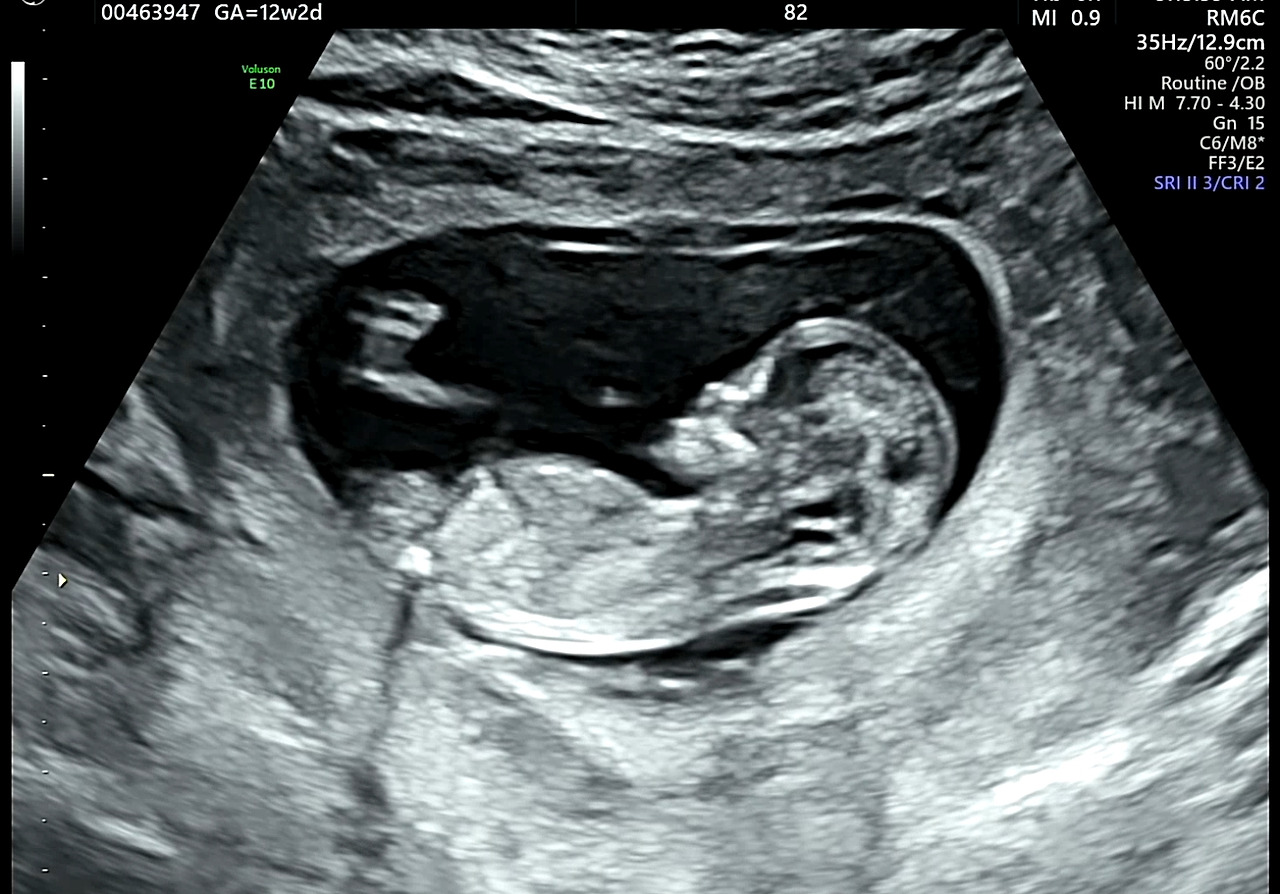

12주 : 기형아검사...

12주에 실시하는 기형아검사는 과거에는 선택항목이었지만 요즘에는 산부인과에서 선택여부를 묻지 않고 실시하는 것 같다. 검사종류는 기본검사와 니프티검사 두 가지가 있는데 둘 다 확률검사로 정확도가 높은 니프티검사가 비싸다. 두 가지 검사에서 고위험군으로 뜨면 확정검사인 양수검사를 실시한다. 노산인지라 의사는 정확도가 높은 니프티검사를 권했고 나는 검사를 하지 않겠다고 말했다.

내막은 이렇다. 노산이어서 기형아에 대한 걱정으로 그동안 기형아검사에 대해 끊임없이 인터넷으로 알아봤다. 기본검사에서 고위험군으로 나오면 확정검사인 양수검사를 실시하는데, 알아본 바로는 고위험군이어도 대부분 양수검사에서 정상판정을 받았다. 그런데,, 문제는 양수검사결과가 나오기까지 임산부가 엄청난 스트레스를 겪는다는 것이다. 울음으로 소중한 하루하루를 보낸다는 것이 너무 안타까웠다.

12주에 실시하는 목투명대검사에서 정상수치가 나왔고, 의사에게 아기를 믿고 검사를 하지 않겠다고 말씀드리니 의사도 내 의사를 존중해 주었다. 검사결과에 마음 졸이지 않고 마음 편히 지내는 쪽을 선택했다.

투명대검사에서 정상수치가 아니더라도 기형아가 아닌 경우도 많으니 산모들이 너무 스트레스를 안 받았으면 한다.